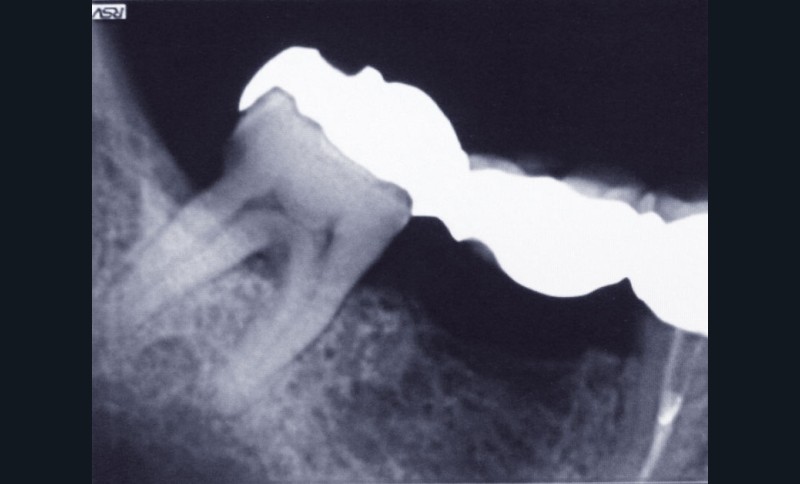

Un patient se présente pour le descellement d’un bridge 45-47 au niveau de l’onlay en 47 (fig. 1).

Afin de préserver la 45, il lui est proposé de couper le bridge en distal de 45 et en mésial de 47, de resceller l’onlay sur 47 et de poser un implant au niveau de 46, cela afin d’éviter un inévitable redescellement de la prothèse (fig. 2).

La perte osseuse vestibulaire dans ce secteur (fig. 3) ainsi…